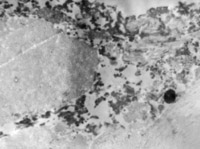

5-2-1 傷后第1天,表皮凝固性壞死,真皮淺層膠原纖維變性  HE×100